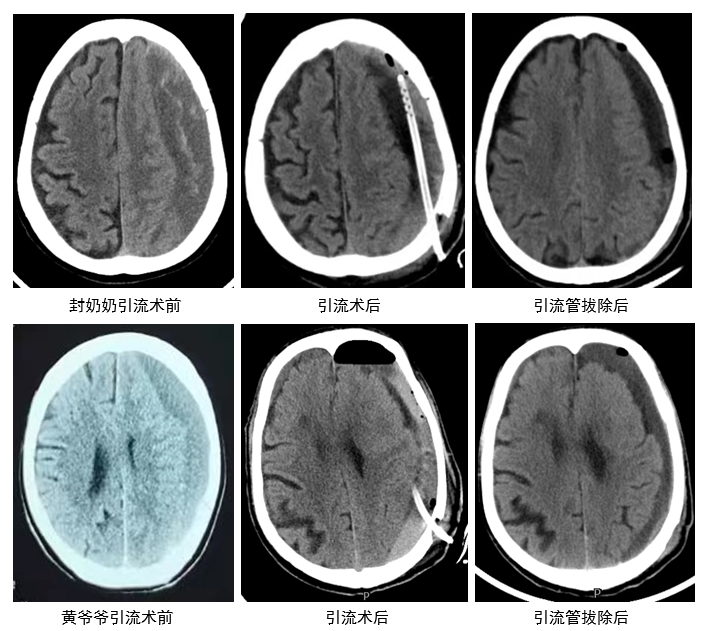

82岁的封奶奶,在我院风湿病科住院期间出现右侧肢体活动不利伴言语不利,头颅CT显示左硬膜下血肿、左大脑受压、大脑镰下疝,科室急请针灸/康复/神经内科刘桂林主任医师会诊,会诊后当即决定转科行手术治疗。

刚刚结束会诊,刘桂林就接到了科室二线手机紧急呼叫,飞快跑向了门诊。72岁的黄爷爷,因“突发右侧肢体活动不利1天”在门诊就诊,刘桂林面诊后,带患者完善头颅CT示左硬膜下血肿,当即决定收入病房行手术治疗。

经详细问诊,两位患者有跌倒史,结合影像检查结果,均诊断为“慢性创伤性硬膜下血肿”,收入病房后,王雪飞副主任医师即带杜鑫主治医师、赵冰骢主治医师两位接诊医师对病人进行细致的神经系统专科查体,并向患者家属交代病情。温雅丽副主任医师紧急联系沟通手术室、麻醉科,医护团队完成术前准备工作。麻醉科主任丁玲玲、护士长文玉琴积极安排手术,刘桂林主刀、王雪飞协助为两位患者顺利完成“立体定向颅内血肿硬通道穿刺引流术”,手术时长均不到1小时,术中出血不到10ml。